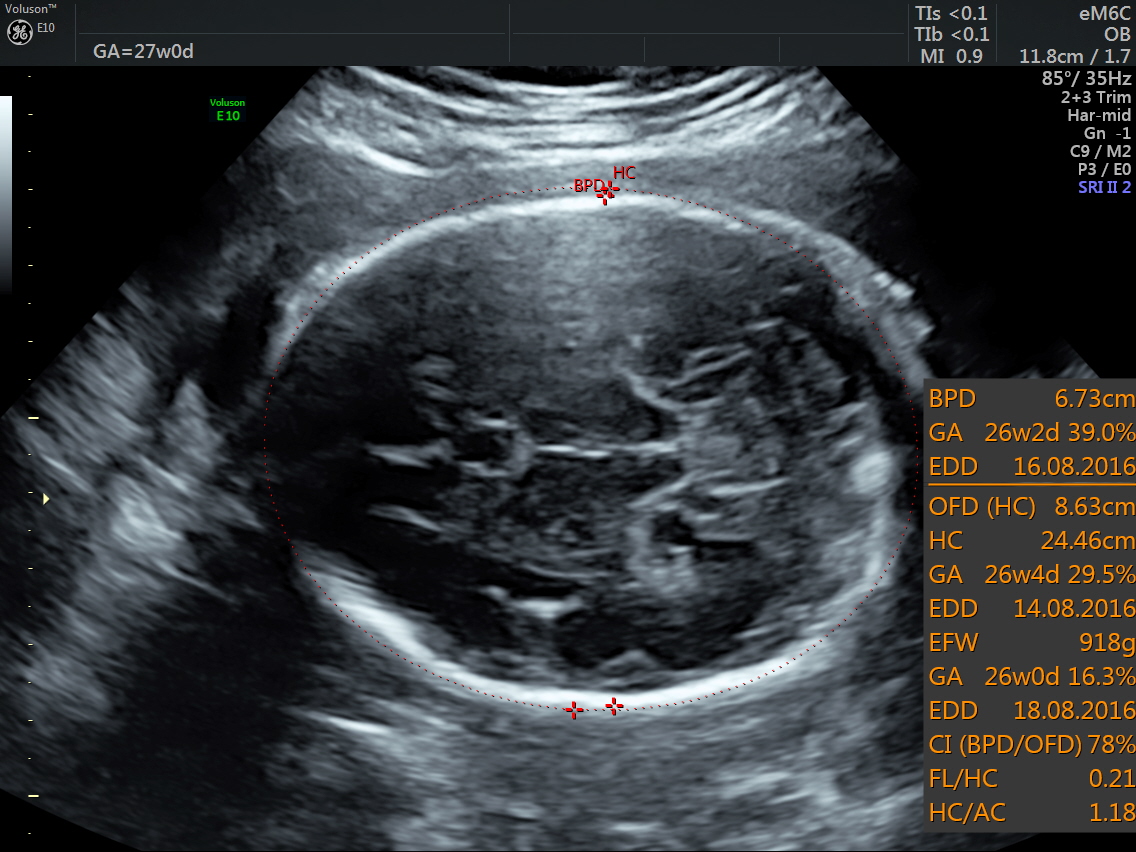

RT AORTIC ARCH_3 Published June 17, 2016 at 1136 × 852 in Rt aortic arch and aberrant left subclavian artery ← Previous Next →